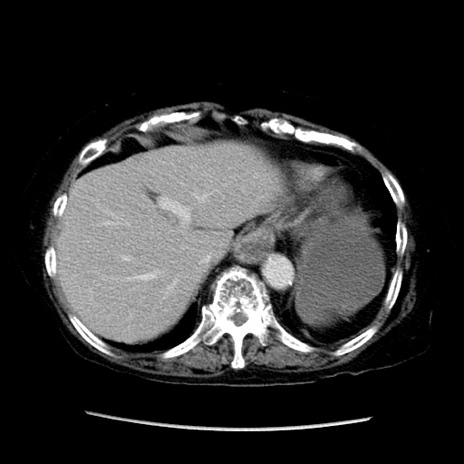

症例14(横断像)

【症例】 90歳代女性

【主訴】 腹痛・嘔吐

【現病歴】今朝から左側腹部痛を認めた。 経過観察していたが、嘔吐を認めたため来院。

【既往歴】 子宮癌術後

【身体所見】 意識清明、BP 127/54mmHg、P 98bpm Sp02 95%(RA)、BT 35.8°C、腹部平坦・軟腸ぜん動音聴取良好、右下腹部圧痛(+) 反跳痛なし

【データ】WBC 9800、CRP 0.46